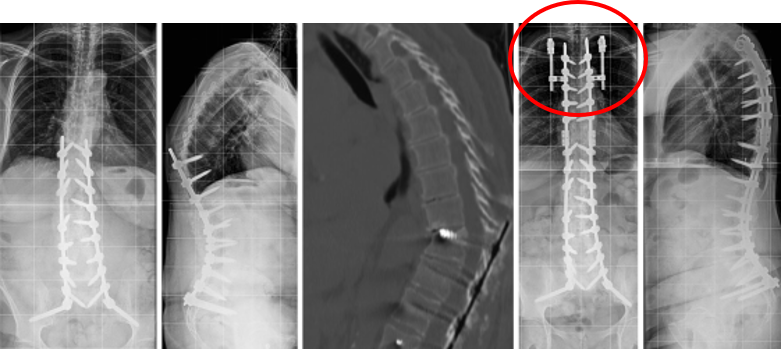

T10骨盆固定,出现交界性后凸

行翻修手术:T9/10SP截骨,延长到T4固定,预防性双侧肋骨固定(VEPTR)

图32-33 肋骨固定